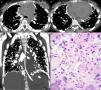

Axial computed tomography images at the level of the bronchial bifurcation (A) and lower lobes (B), and a coronal reformatted image (C) showing several calcified nodules in the subpleural regions and along fissures. Note also mediastinal lymph node calcifications and pericardial effusion. (D) Histological section showing proliferation of neoplastic cells with bone tissue formation. Note also nuclear atypia (hyperchromasia and karyomegaly) (hematoxylin and eosin stain, ×400).

A 14-year-old girl was admitted with a 30-day history of painful swelling in the left knee that had not improved with the use of analgesics and nonsteroidal anti-inflammatory drugs. An X-ray showed an aggressive osteolytic lesion in the left distal femur. Open biopsy examination revealed a proliferation of neoplastic osteoblasts producing abundant irregular osteoid matrix. The diagnosis of osteosarcoma was made. The patient started chemotherapy, but did not show good response to treatment, as the disease remained stable. Five months after diagnosis, she presented chest pain and respiratory distress. Chest computed tomography revealed several irregular calcified nodules and plaques in the subpleural regions of the lungs, as well as pericardial effusion (Fig. 1). Thoracoscopy showed numerous subpleural nodules. The histopathological diagnosis was metastatic osteosarcoma. A few days later, the patient's condition worsened, with severe dyspnea, and she died. Autopsy was performed and confirmed the lymphatic dissemination of the tumor cells.